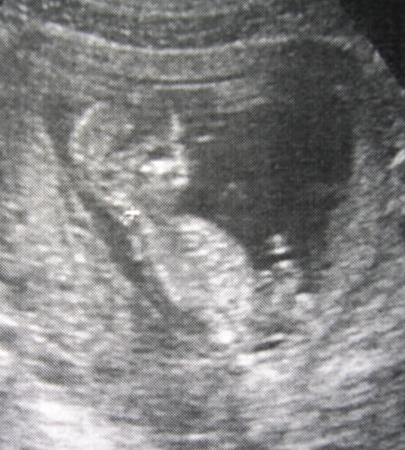

и кулочек сжимали)))) и палbчик в ротик засовывали))))) а потом голову почисали))))хахахаахха..так приколbно было....мужа сразу решил что это замашки парня)))))как буд-то он лежит на диване и чешит голову)))))))) потом мы вертелисb..крутилисb....а там видимо захотели кушатb..и подняли бунт на корабле..начали мохатb руками и ногами...))))))Вообшем сказали что у нас все хорошо,и воротниковая зона нормалbная..и носовая костb на месте(что исключает синдром дауна), и плацента у нас хорошая..и тонуса нет....ВСЕ СУПЕР!!!! А еще девочки...нам его сфотографировали и напечатали...и еще даже видео записали..правда дисков не оказалосb...я потом сама схожу скину видео...но это такое счастbе...у меня прям слезки проступили от счастbя)))))))

это мы палbчик в рот засунули с голодухи)))))